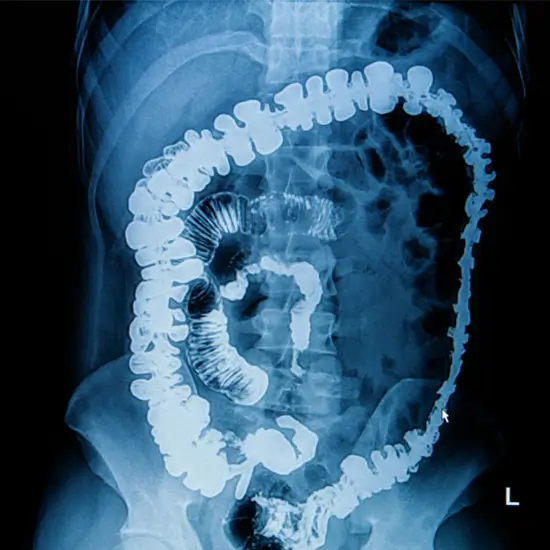

X-Ray Total Barium Meal

The Total Barium Meal test enables your physician to examine the back of your mouth and throat, also known as the pharynx, and the tube that extends from the back of your tongue to your stomach, also known as the esophagus.

A radiologist can analyze and diagnose a wide variety of medical conditions, including the following, simply by looking at the images.

• • Irregularity in the form of the digestive tract

• • Regions where the digestive tract has shrunk and become more restricted.

• • Ulceration

• • Harm is done to the lining of the digestive tract.